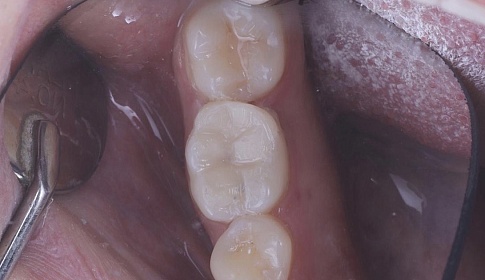

- Формирование фотокомпозитами пломбы.

- Засвечивание пломбы специальными ультрафиолетовыми лампами.

- Проверка смыкания челюстей, при необходимости – коррекция прикуса.

- Шлифование, полирование.